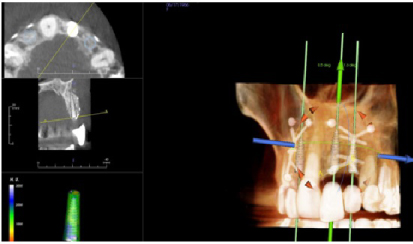

Four months later a new CBCT of the maxillary arch was completed and at all sites, #s 7. 9, and 10 with successful GBR achieved and implant placement was planned using the Anatomage (San Jose, CA, USA) implant planning software (Figures 17, Figure 18, and Figure 19). Each site went from less than 2 mm of width preoperatively to a width of 7 mm four month after grafting.

Figure 17: Post-op four months grafting #7 site CBCT and Anatomage implant planned. Notice the increased bone width from a preoperative width of less than 2 mm to a width greater than 6 mm. View Figure 17

Figure 18: Post-op four months grafting #9 site CBCT and Anatomage implant planned. Notice the increased bone width from less than 2 mm to 7 mm. View Figure 18